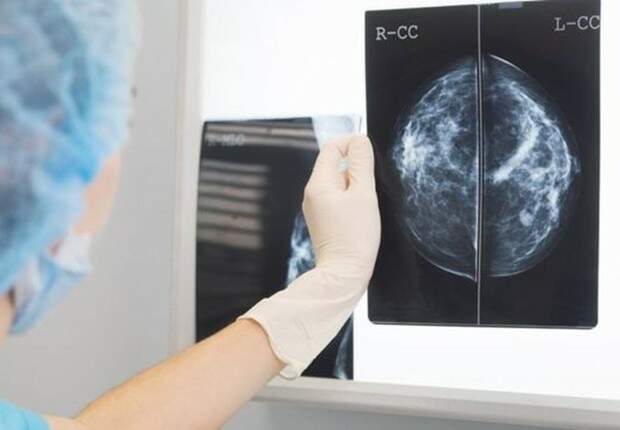

Apesar do crescimento no número de exames de mamografia no ano passado, ainda são poucas as mulheres que conseguem ter acesso ao diagnóstico precoce do câncer de mama.

O número de exames tem caído. Foram pouco mais de 6,1 milhões em 2019 e 3,7 milhões em 2020. No ano passado, aumentou um pouco: 5,2 milhões.

“Nós estamos muito longe do ideal, porque como se sabe, em 2019, antes da pandemia, os números já não eram bons. O que nós precisamos para fazer realmente uma diminuição no número de mortes é fazer um programa nacional de rastreamento mamográfico com busca ativa e não só ter recomendações”, afirma Maira Caleffi, presidente voluntária da Femama.

É assustador ouvir que, em cada dia deste ano, 181 brasileiras vão receber a notícia de que estão com câncer de mama. Pois essa é a projeção do Instituto Nacional do Câncer, que estima mais 66 mil novos casos para 2022.

“É garantido por lei o direito da mulher brasileira a fazer o rastreamento mamográfico a partir dos 40 anos de idade. Por mais que o Inca e o Ministério da Saúde recomendem que esse exame seja feito a partir dos 50 anos de idade de forma bianual. Então a mulher brasileira pode solicitar ao seu médico que a atende a realização do exame mamográfico”, explica o presidente da Sociedade Brasileira de Mastologia, Vilmar Marques de Oliveira.